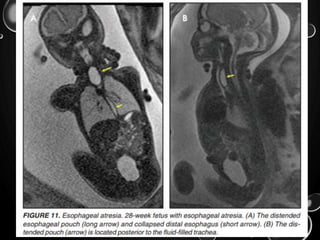

ESOPHAGEAL ATRESIA

• ESOPHAGEAL ATRESIA WITH OR WITHOUT DISTAL FISTULA IS

A DIFFICULT DIAGNOSIS TO MAKE PRENATALLY AND IS

USUALLY BASED ON INDIRECT FINDINGS THAT INCLUDE

POLYHYDRAMNIOS CAUSED BY OBSTRUCTION OF FETAL

SWALLOWING, A PERSISTENTLY SMALL STOMACH AND

POSSIBLY, BUT RARELY SEEN, A DILATED UPPER ESOPHAGEAL

POUCH .

• ABOUT HALF- OTHER ASSOCIATED ANOMALIES GROUPED

UNDER THE ACRONYM OF VACTERL (VERTEBRAL DEFECTS,

ANAL ATRESIA, CARDIAC ANOMALIES, TRACHOESOPHAGEAL

FISTULA, RADIAL DEFECTS, RENAL, AND LIMB,